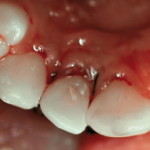

Frattura corono-radicolare: gestione di un caso clinico

Per definizione, le fratture corono-radicolari coinvolgono lo smalto, la dentina e il cemento. Si presentano raramente, con una frequenza del 5% in dentizione permanente...